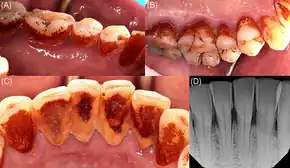

| Complications | Addiction, mouth cancer, tooth decay, heart disease[3][2] |

Chewing betel quids and areca nut causes multiple forms of cancer and cardiovascular disease, regardless of tobacco use.[6][9][10][11] Increased risks include head and neck cancers and esophageal cancer.[12][13][14] It affects the brain, heart, lungs, gastrointestinal tract and reproductive organs. It can cause myocardial infarction, cardiac arrhythmias, liver damage, asthma, type II diabetes, hyperlipidemia, metabolic syndrome, low thyroid, prostate enlargement and infertility.[15]

When chewed with additional tobacco in its preparation (like in gutka), there is an even higher risk for cancer, especially for oral and oropharyngeal cancers.[8]